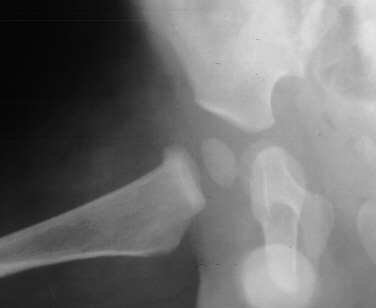

- Hospital Day 6: Respiked to 103.4. R hip Xray showed a defect in proximal

medial metaphysis, Possible osteomyelitis. The child was than taken to

the operating room for Incision & Drainage of Right hip via anterolateral

approach with suction irrigation system (seropurulent fluid drained).

- Post Operative Day 7: Drains removed. Respiked to 101.6. R hip Xray:

suggestion of demineralization of proximal metaphysis. The hip was reaspirated

- Post Operative Day 18: R hip Xray: subluxation of R hip, possible metaphyseal

lucency consistent with osteomyelitis. Taken to OR for repeat I & D

. metaphysis including lucency and demineralization, hip subluxated. Treated

with oxacillin and Pavlik harness.

- 2 month Office Follow Up: Rt hip Xray: progressive destruction of capital

femoral epiphysis, cystic changes in metaphysis consistent with AVN.